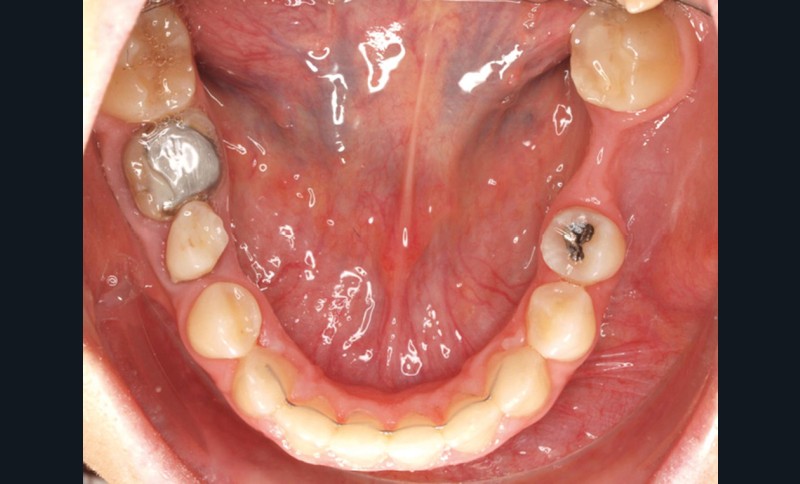

Diagnostic (fig. 1a-g)

La patiente présente une classe III squelettique dans un contexte hyperdivergent associée à une endoalvéolie maxillaire, un articulé inversé antérieur, une rétroversion incisive maxillaire, des rapports de classe I canine bilatérale, une absence de 16 et 36.

Le sourire est étroit, dégradé par les malpositions dentaires.